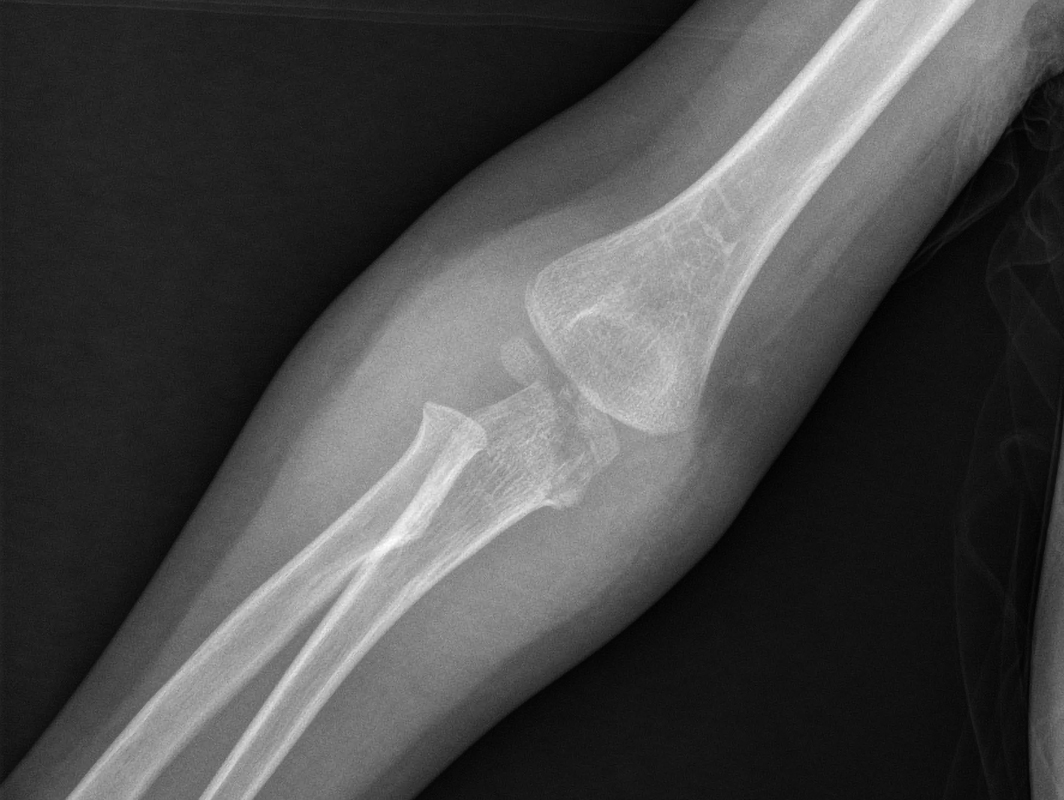

Le fratture metafisarie di olecrano (Figg. 1, 2) invece sono più frequenti, legate a tre meccanismi diversi:

- Traumi diretti a gomito flesso

In queste fratture accade che la forza tricipitale prossimale e la forza del muscolo brachiale distale aumentino la suscettibilità della corticale olecranica posteriore che quindi facilmente si rompe con linee fratturative trasverse intrarticolari.

- Traumi a gomito esteso con stress in varo o valgo

In accrescimento è frequente trovare una condizione di iperlassità legamentosa che, in caso di traumi a gomito esteso, favorisce lo sviluppo di fratture sovracondiloidee. L’olecrano distale può essere interessato quando il gomito oltre ad essere iperesteso è anche stressato in varo o valgo. Si tratta di fratture tipicamente lineari ed extrarticolari, a “legno verde”.

- Traumi con fratture da forza di taglio

Si tratta di fratture rare, generate da traumi diretti all’olecrano che causano una forza di trazione anteriore, a seguito della quale il frammento distale si disloca anteriormente. La rima di frattura può essere trasversa o obliqua.